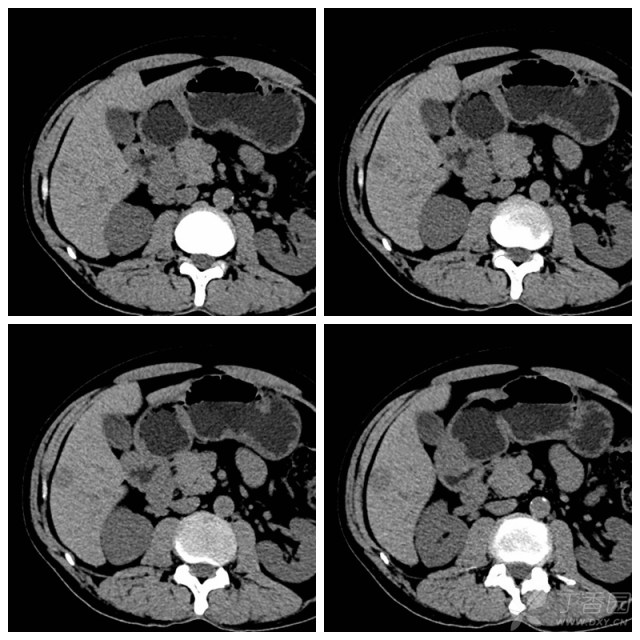

肝癌:增强ct,典型"快进快出".

图片尺寸640x480